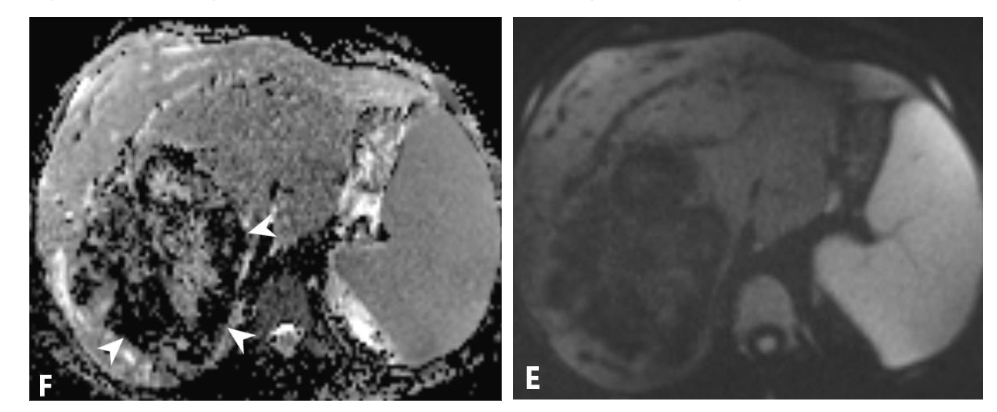

A 17-year-old female, previously healthy, presented with abdominal pain and pruritus for several months. She noticed jaundice in her eyes for the last two weeks but denied acholic stools. These symptoms were associated with a 10-pound weight loss and fatigue. She was not on any steroids or oral contraceptive pills. Initial lab data showed a total bilirubin of 4.7 mg/dL (0.0-1.2), alkaline phosphatase of 390 unit/L (40-130), AST of 101 unit/L (10-45), and ALT of 162 unit/L (7-45). Abdominal ultrasound (Figure 1) showed a large lobulated mixed echogenicity mass centered on the right hepatic lobe containing several hypoechoic components with posterior acoustic shadowing without a discernible central scar. Color Doppler showed scanty peripheral vascularity without significant internal vascularity. The spleen was moderate to markedly enlarged with a craniocaudal dimension of approximately 19 cm. Upon further laboratory evaluation, CA 19-9 was 68.8 units/mL (Nl: up to 35) with normal serum alpha-fetoprotein and beta-HCG. Abdominal MRI (Figure 2) showed a large, predominantly T1/T2 hypointense mass with delayed progressive enhancement (Figure 3). There was no signal drop throughout the lesion on out-of-phase images to suggest a fat component. DWI and ADC mapping demonstrated a predominantly hypointense signal (T2 blackout). No central scar was appreciated within the hepatic lesion. Mild, regular dilation of peripheral intrahepatic biliary ducts was also identified due to the mass effect on the biliary system. Splenomegaly and collateral vessels were present. There was no tumoral invasion or thrombosis of the inferior vena cava.

Figure 3. Axial T1 WI without contrast (A) and T1 WI immediate post contrast (B) show lack of early arterial enhancement. Axial T1WI 5 minutes post contrast (C) shows foci of enhancement which become more confluent and pronounced on axial T1WI 20 minutes post contrast (D).

Delayed Contrast Enhancement: Delayed contrast enhancement, a hallmark imaging feature of fibrous tumors¹³,¹⁴, is also evident in this case.

HCC and hepatoblastoma are very unlikely the absence of underlying liver disease and considering patient’s age, respectively. Furthermore, progressive contrast enhancement on delayed images rather than early arterial enhancement argues against HCC. Moreover, there was no central scar to support the diagnosis of fibrolamellar HCC¹⁵.